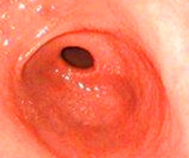

在郑州益好医院治愈的萎缩性胃炎患者

第一次检查萎缩性胃炎发生 病变、胃粘膜受损

第二次复查萎缩性胃炎中度

第三次复查完全康复